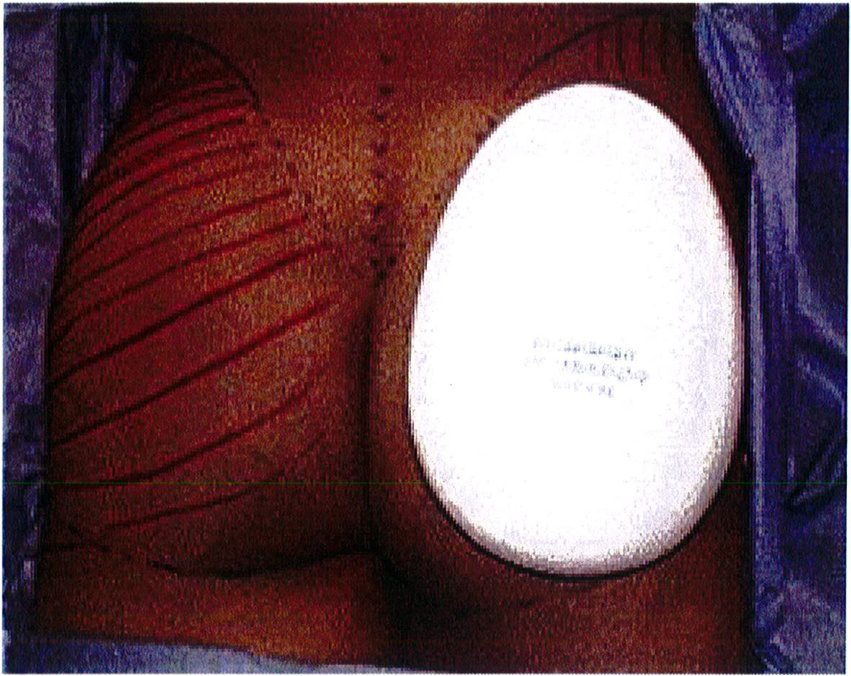

Hình. 7. Đặt sizer lên trên vùng mông để ước lượng vị trí khối implant. (Trích từ de la Pena JA. Subfascial technique for Gluteal Augmentation. Aesthet Surg J 2004;24:268; đã xin phép trước khi đăng tải.)

rằng cả hai bên túi được bóc tách trước khi đặt mô cấy để dễ dàng căn chỉnh hai bên cho cân đối (Hình 12 và 13). Sau khi bóc tách xong, sử dụng các sizer đặt vào mặt phẳng vừa bóc tách để xác nhận lại kích thước khối implant phù hợp cho bệnh nhân (Hình 14).

Hình. 14. Sau khi hoàn thành việc đặt túi, hãy đặt 1 sizer vào để đánh giá tính cân đối và thể tích khoảng không gian bên trong đó. Chú ý khối implant phải vừa khít với túi. (From de ia Pena jA, Kubio ÜV, Cuno JP, et al. Subfascial Näng mong. Clin Plast Surg 2006; 33:414; đã xin phép trước khi đăng tải.)